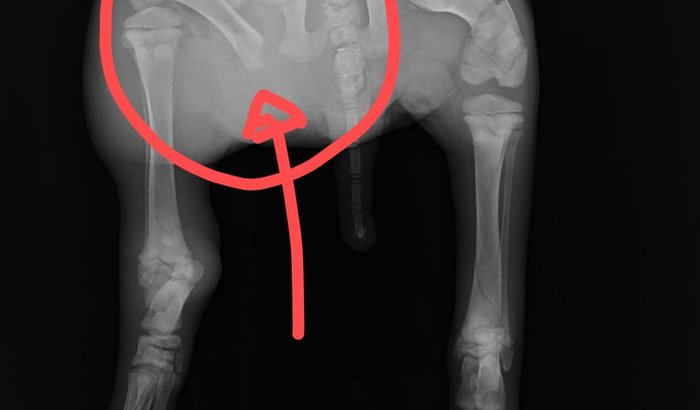

Temos feito tudo o que está ao nosso alcance para salvá-lo. Conseguimos consulta e exames cm valor acessível no HOVET Hospital Veterinário da Uninorte. No entanto, os exames indicaram uma fratura delicada de fêmur (conforme podem ver na foto do raio x) com indicação de cirurgia e também está anêmico. Compramos vários medicamentos por conta própria, mas agora precisamos mesmo de ajuda com os custos. O cãozinho irá necessitar de consulta especializada com um Vet Ortopedia para avaliar e ver quanto cobraria pela cirurgia. Os veterinários que o atenderam até o momento, já nos informaram que uma cirurgia como esta, custa no mínimo 2,000.00 e ainda teremos os custos com outras consultas e medicamentos. O filhote foi batizado de "Plinio". A pata do Plinio está muito inchada (edema nas costas, pata e abdomem) e cada vez que ele se mexe, solta muitos gritos de dor.